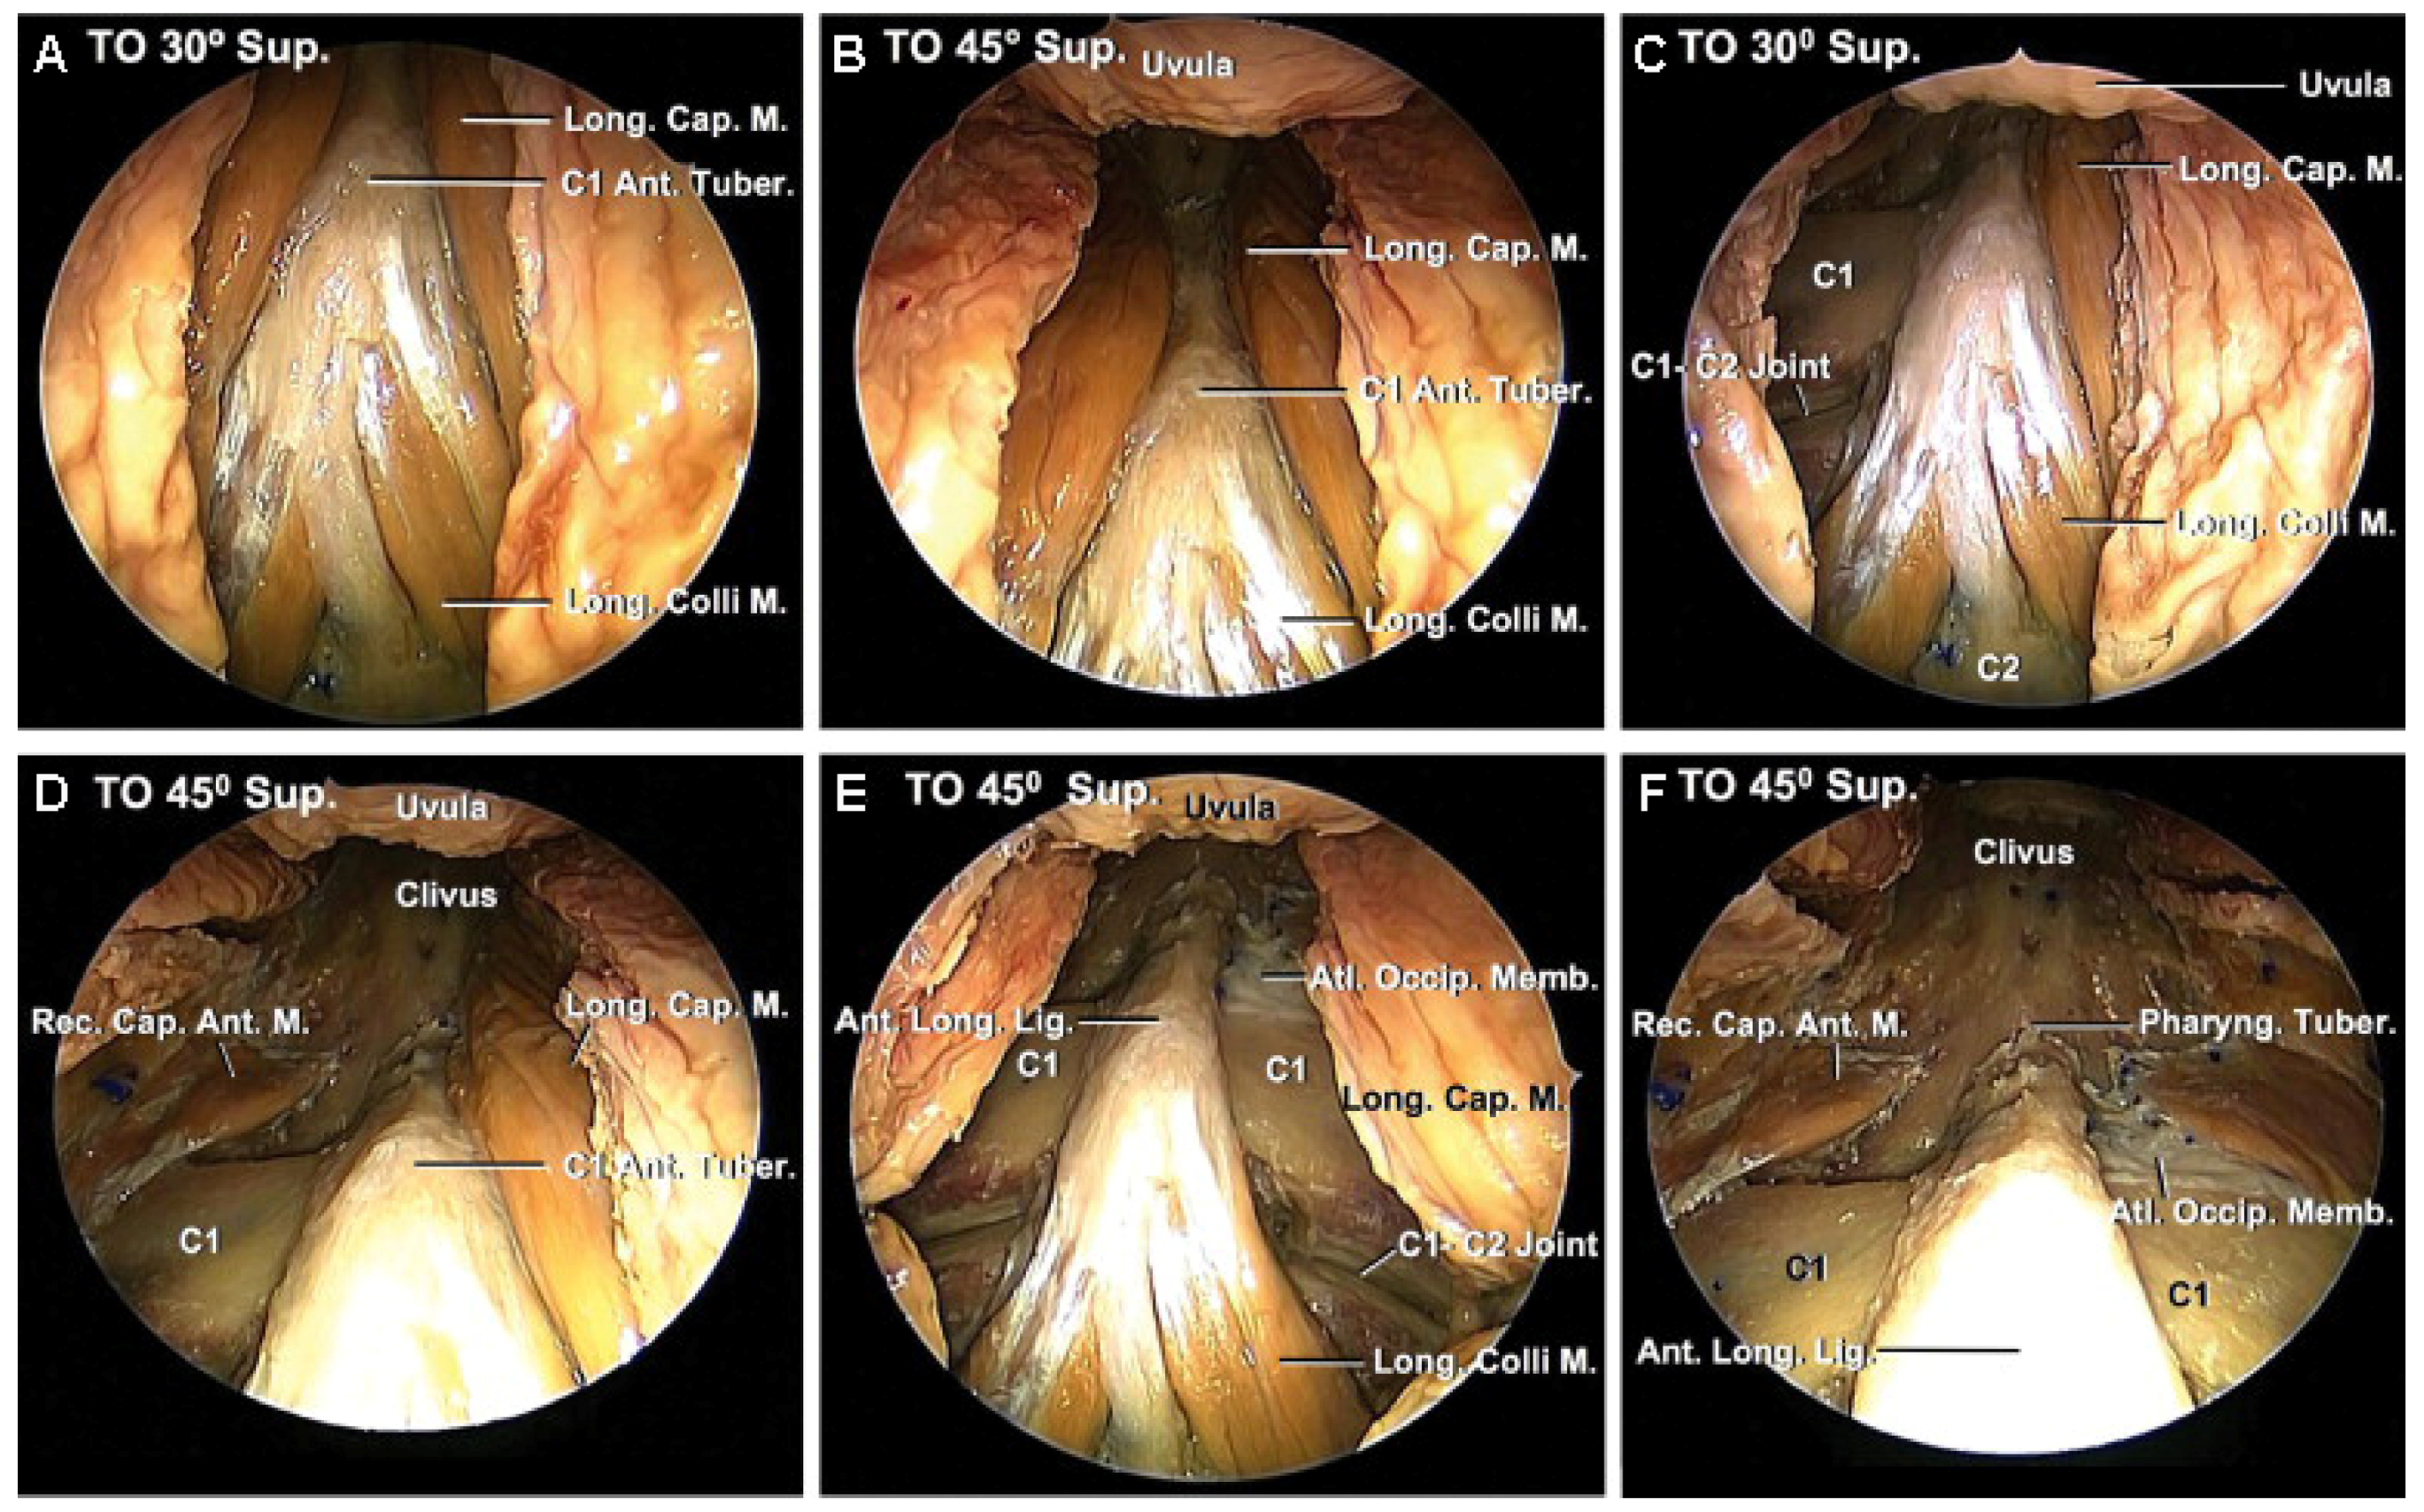

2. Endonasal Cervical Approaches for Pathologies of the Upper Cervical Spine

- Seker, A.; Inoue, K.; Osawa, S.; Akakin, A.; Kilic, T.; Rhoton, A.L. Comparison of Endoscopic Transnasal and Transoral Approaches to the Craniovertebral Junction. World Neurosurg. 2010, 74, 583–602. [Google Scholar] [CrossRef] [PubMed]